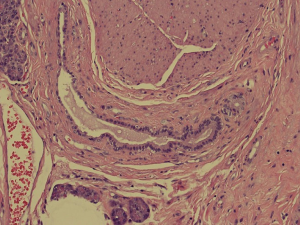

Histopathological analysis of the specimen revealed complete excision of the mass, which was reported to be benign pancreatic tissue, showing both endocrine and exocrine elements (islets of Langerhans, pancreatic acini, and pancreatic ducts) (Figures 4-9). No atypical features were seen and there was no evidence of malignancy.

The histological morphology of EP tissue can be classified according to Heinrich’s criteria, proposed in 1909 (9). Type 1 EP tissue contains cells of exocrine glands, excretory ducts and islets of Langerhans; type 2 contains only excretory glands and excretory ducts; type 3 contains only excretory ducts (8). In 1973, Gasper-Fuentes proposed a modified version of the Heinrich criteria, comprising of four types of EP tissue:

- Type I: typical pancreatic tissue composed of acini, ducts and islet cells;

The patient reported herein is classified under type I.